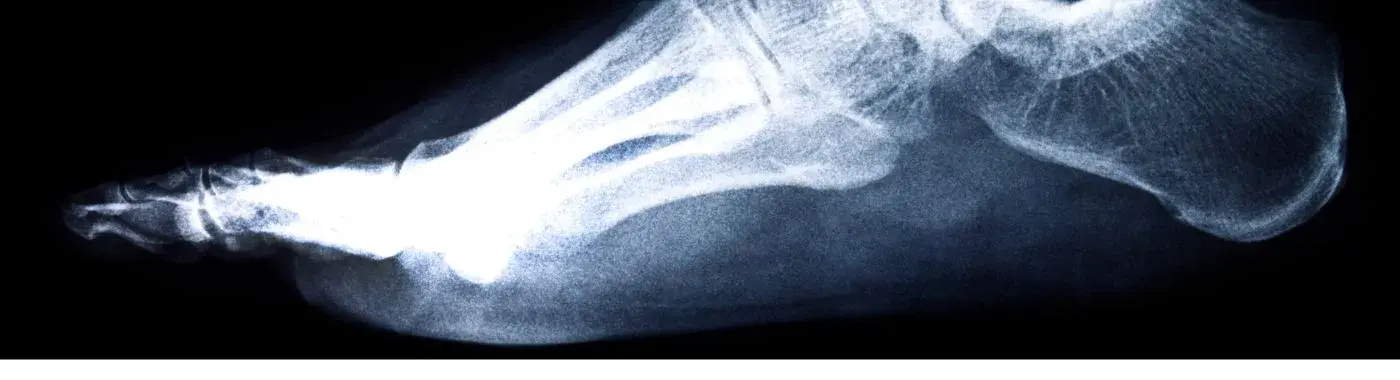

A talus fracture refers to a break in the talus bone, which is located above the heel bone (calcaneus) and below the tibia and fibula (the two long bones of the lower leg). The talus is unique because it does not have any muscle attachments; instead, it is surrounded by ligaments and is crucial for the ankle's range of motion. Talus fractures can occur in various ways, including through high-impact injuries, falls, or repetitive stress.

1. Imaging Studies: X-rays are the primary imaging tool used to confirm a talus fracture. In some cases, a CT scan or MRI may be necessary to assess the extent of the injury and any associated damage to surrounding tissues.